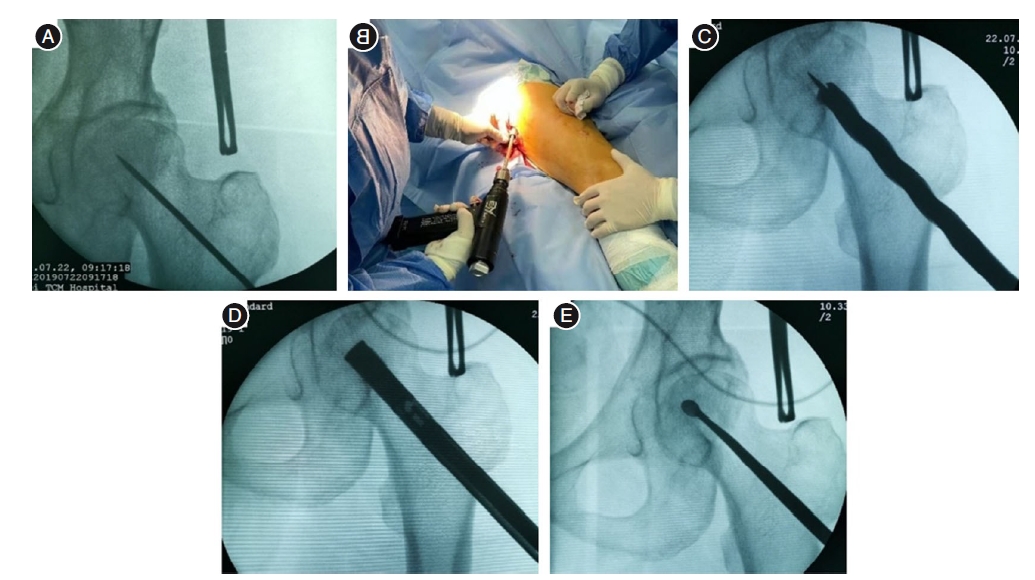

Core decompression combined with BMP activity inducing rod implantation for early femoral head necrosis

Objective To investigate the effect of core decompression combined with bone-morphogenetic proteins (BMP) activity inducing rod implantation in the treatment of early-stage femoral head necrosis. Methods Retrospective analysis of 116 patients with early-stage femoral head necrosis from June 2018 to June 2022 were divided into core decompression combined with BMP activity inducing rod group (BMP group) and allograft bone group. Sixty cases in the BMP group were treated with core decompression combined with implantation of BMP-activated induced rods, and 56 cases in the allograft group were treated with core decompression combined with bone grafting of the allograft bone by punching and compression.The differences in hip Harris scores and visual analogue scores (VAS) of pain between the two groups at preoperative, 6 months postoperative and 1 year postoperative, and the patient treatment response and femoral head survival rate at 1 year postoperative were compared. Results All patients were followed-up, and the difference between the preoperative VAS score and Harris score of the two groups was not statistically significant (P > 0.05), and the VAS score and Harris score of the two groups were significantly improved at 6 months and 1 year after operation, and the BMP group was better than the allograft bone group, with significant difference(P < 0.05). At 1 year after surgery, the Harris hip score excellence rate of the BMP group was higher than that of the allograft bone group, and the difference was statistically significant (P < 0.05); the femoral head survival rate of the BMP group was higher than that of the allograft bone group, and the difference was statistically significant (P < 0.05). Conclusions Core decompression combined with BMP activity induced rod implantation was effective in the treatment of early femoral head necrosis, which accelerated the induction of new bone formation, improved the quality of new bone, provided biomechanical support for the femoral head, and effectively avoided femoral head collapse. Moreover, it has good biocompatibility and couldbe degraded and absorbed in the body, which is worthy of clinical promotion.